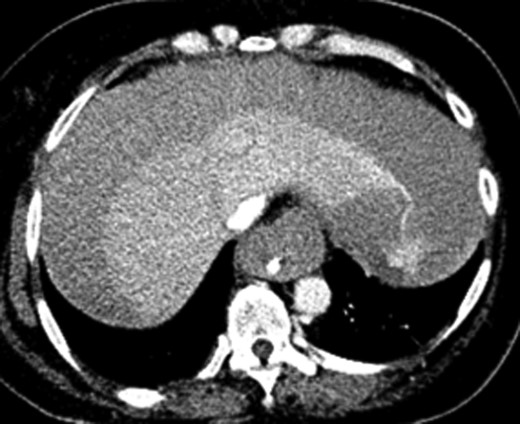

Once stable, imaging confirmed PE (Fig. 2) with a RV to left ventricle (LV) ratio of 2.1 (Fig. 3). The patient was then admitted to the ICU requiring inotropic support. Approximately 4 h later, the patient had concerning features of abdominal compartmental syndrome with increase abdominal distention and bladder pressures >25 mmHg was noted. Repeat imaging showed large volume hemoperitoneum emanating from the left hepatic lobe (Fig. 4). The patient underwent a decompressive laparotomy with a non-anatomic liver resection of segments I and II and temporary abdominal closure. Due to concerns of distal limb ischemia of the arterial cannulation site, an 8-Fr reperfusion cannula was placed in the left superficial femoral artery (SFA).

CTA chest demonstrating significant RV strain with a RV/LV ratio of 2.1.